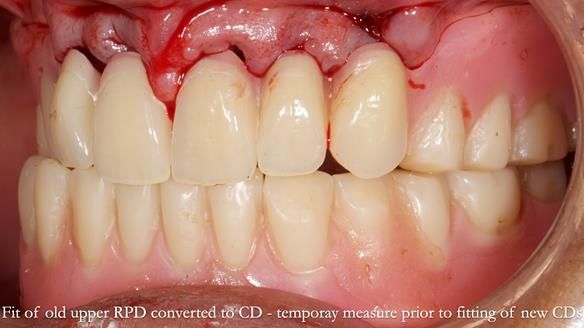

Welcome to Newsletter 62. In this edition, I walk through the process of removing 5 upper anterior teeth, adding to an existing upper RPD, followed by creating and fitting metal based complete dentures for Rafique, a 71 year old man.

The detailed clinical situation and treatment process are outlined below, with clinical work provided by me and technical work by Rowan Garstang. The treatment spanned 12 months, involving removing 5 upper anterior teeth, adding to an existing upper RPD, followed by creating and fitting metal based complete dentures.